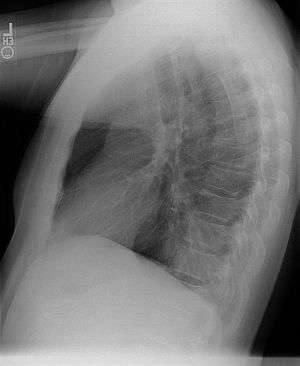

Chest radiograph